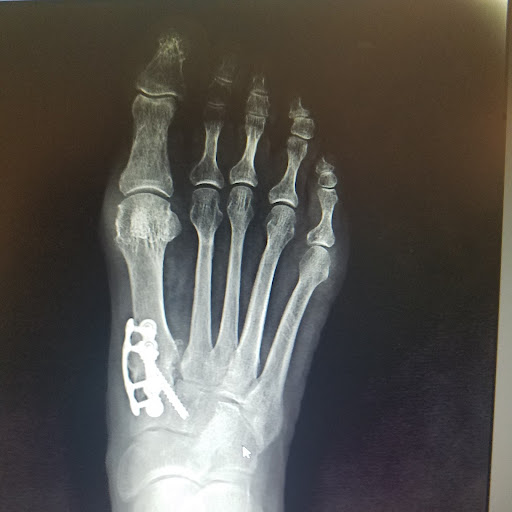

• Trauma Foot & Ankle Surgery

• Ankle Fracture